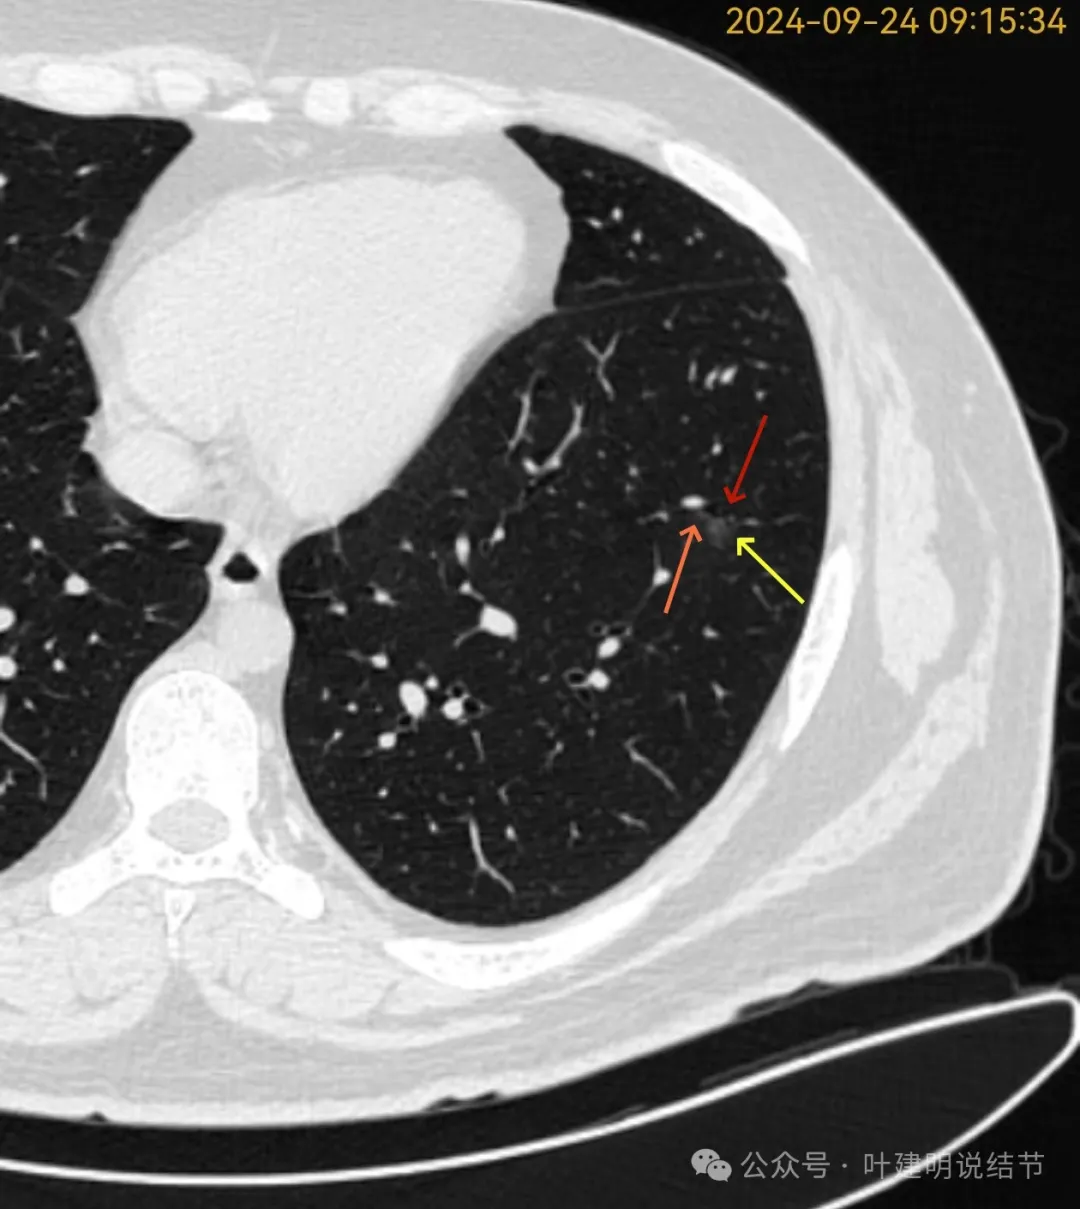

再看2024年9月复查的片子:

病灶出现,磨玻璃密度。有微小血管与细支气管通气征。

邻近细支气管扩张、边缘细毛刺、整体轮廓清。

有毛刺征,整体轮廓清,与血管之间间隙消失。

毛刺、血管征、邻近支气管扩张、整体轮廓清,病灶与血管间隙消失。

有少许偏实性成分,整体轮廓清。

纯磨密度,不太纯,血管贴边,血管与病灶间隙消失,整体轮廓与瘤肺边界清。

血管弯征可见、细毛刺明显、细支气管扩张,血管进入。

密度总体不高,轮廓与边界清楚。

密度较淡,轮廓较清。

边缘区密度淡且较纯,轮廓清楚。

左下这个病灶是磨玻璃密度,不是非常纯,但是仍然也说不上纵隔窗能够看见有实性成分,所以严格意义上仍然是纯磨玻璃密度。有血管贴边、整体轮廓较清、表面不平、病灶内有点状偏高密度、与病灶紧贴的细支气管稍有扩张,应该考虑是肿瘤范畴的,但是对比两次,约8个月时间没有明显变化。大概是原位癌或者微浸润性腺癌可能性大。是否需要干预处理,基于:1、密度与实性成分情况;2、随访进展情况;3、个人心理承受能力情况;4、病灶位置情况(手术导致的创伤与肺功能损失与随访风险之间权衡)。鉴于位置还行能单孔楔形切除、密度不太纯,个人稍倾向于单孔胸腔镜下局部切除。如果还不想开刀,那半年复查随访等再有进展再开应该也关系不太大。意见供参考!